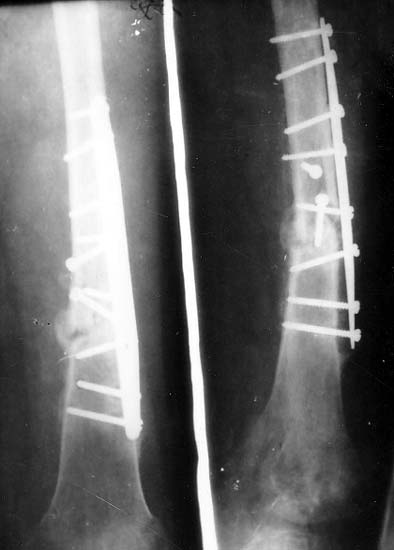

肱骨骨折骨不连6年,大段骨缺损,经异型钢板内固定、植骨,骨生长因子 和骨髓细胞注射方法,成功修复骨缺损